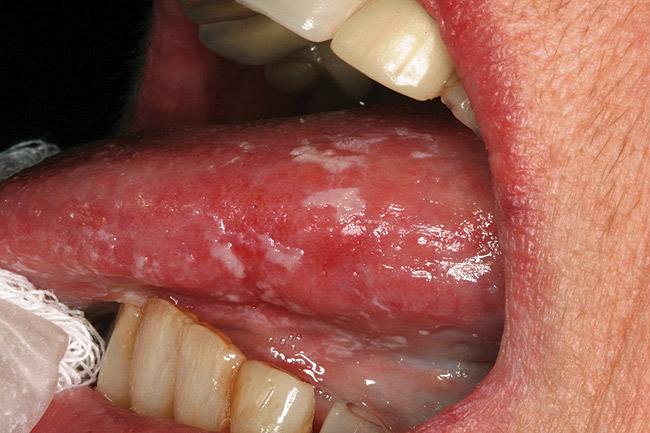

Figure 3  Oral candidiasis (pseudomembranous) is seen as elevated white plaques on the dorsal and lateral surfaces of the tongue.

Figure 3

Saliva aids for oral cavity cleansing, swallowing, taste, speech, and digestion could be compromised in patients with salivary gland hypofunction. The oral mucosa may appear dry and friable. The tongue may appear dry and fissured (Figure 1). Dental caries, plaque accumulation, gingivitis, and periodontitis are common in patients with significant salivary gland hypofunction (Figure 2). Infections, such as oral candidiasis (Figure 3), and enlargement of salivary glands from sialadenitis are seen commonly in patients with moderate-to-severe salivary gland hypofunction (Figure 4). Difficulty in mastication and swallowing also may indicate advanced salivary gland hypofunction19 and can contribute to poor nutrition.20 Denture retention may become difficult because of the lack of saliva12 (Table 3).